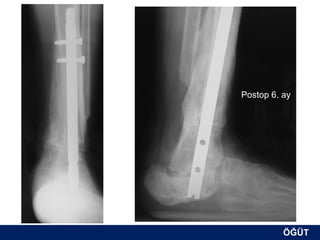

OLGU No 5   H.G., 26y, K

Postop 3. ay

ÖĞÜT

Postop 6. ay